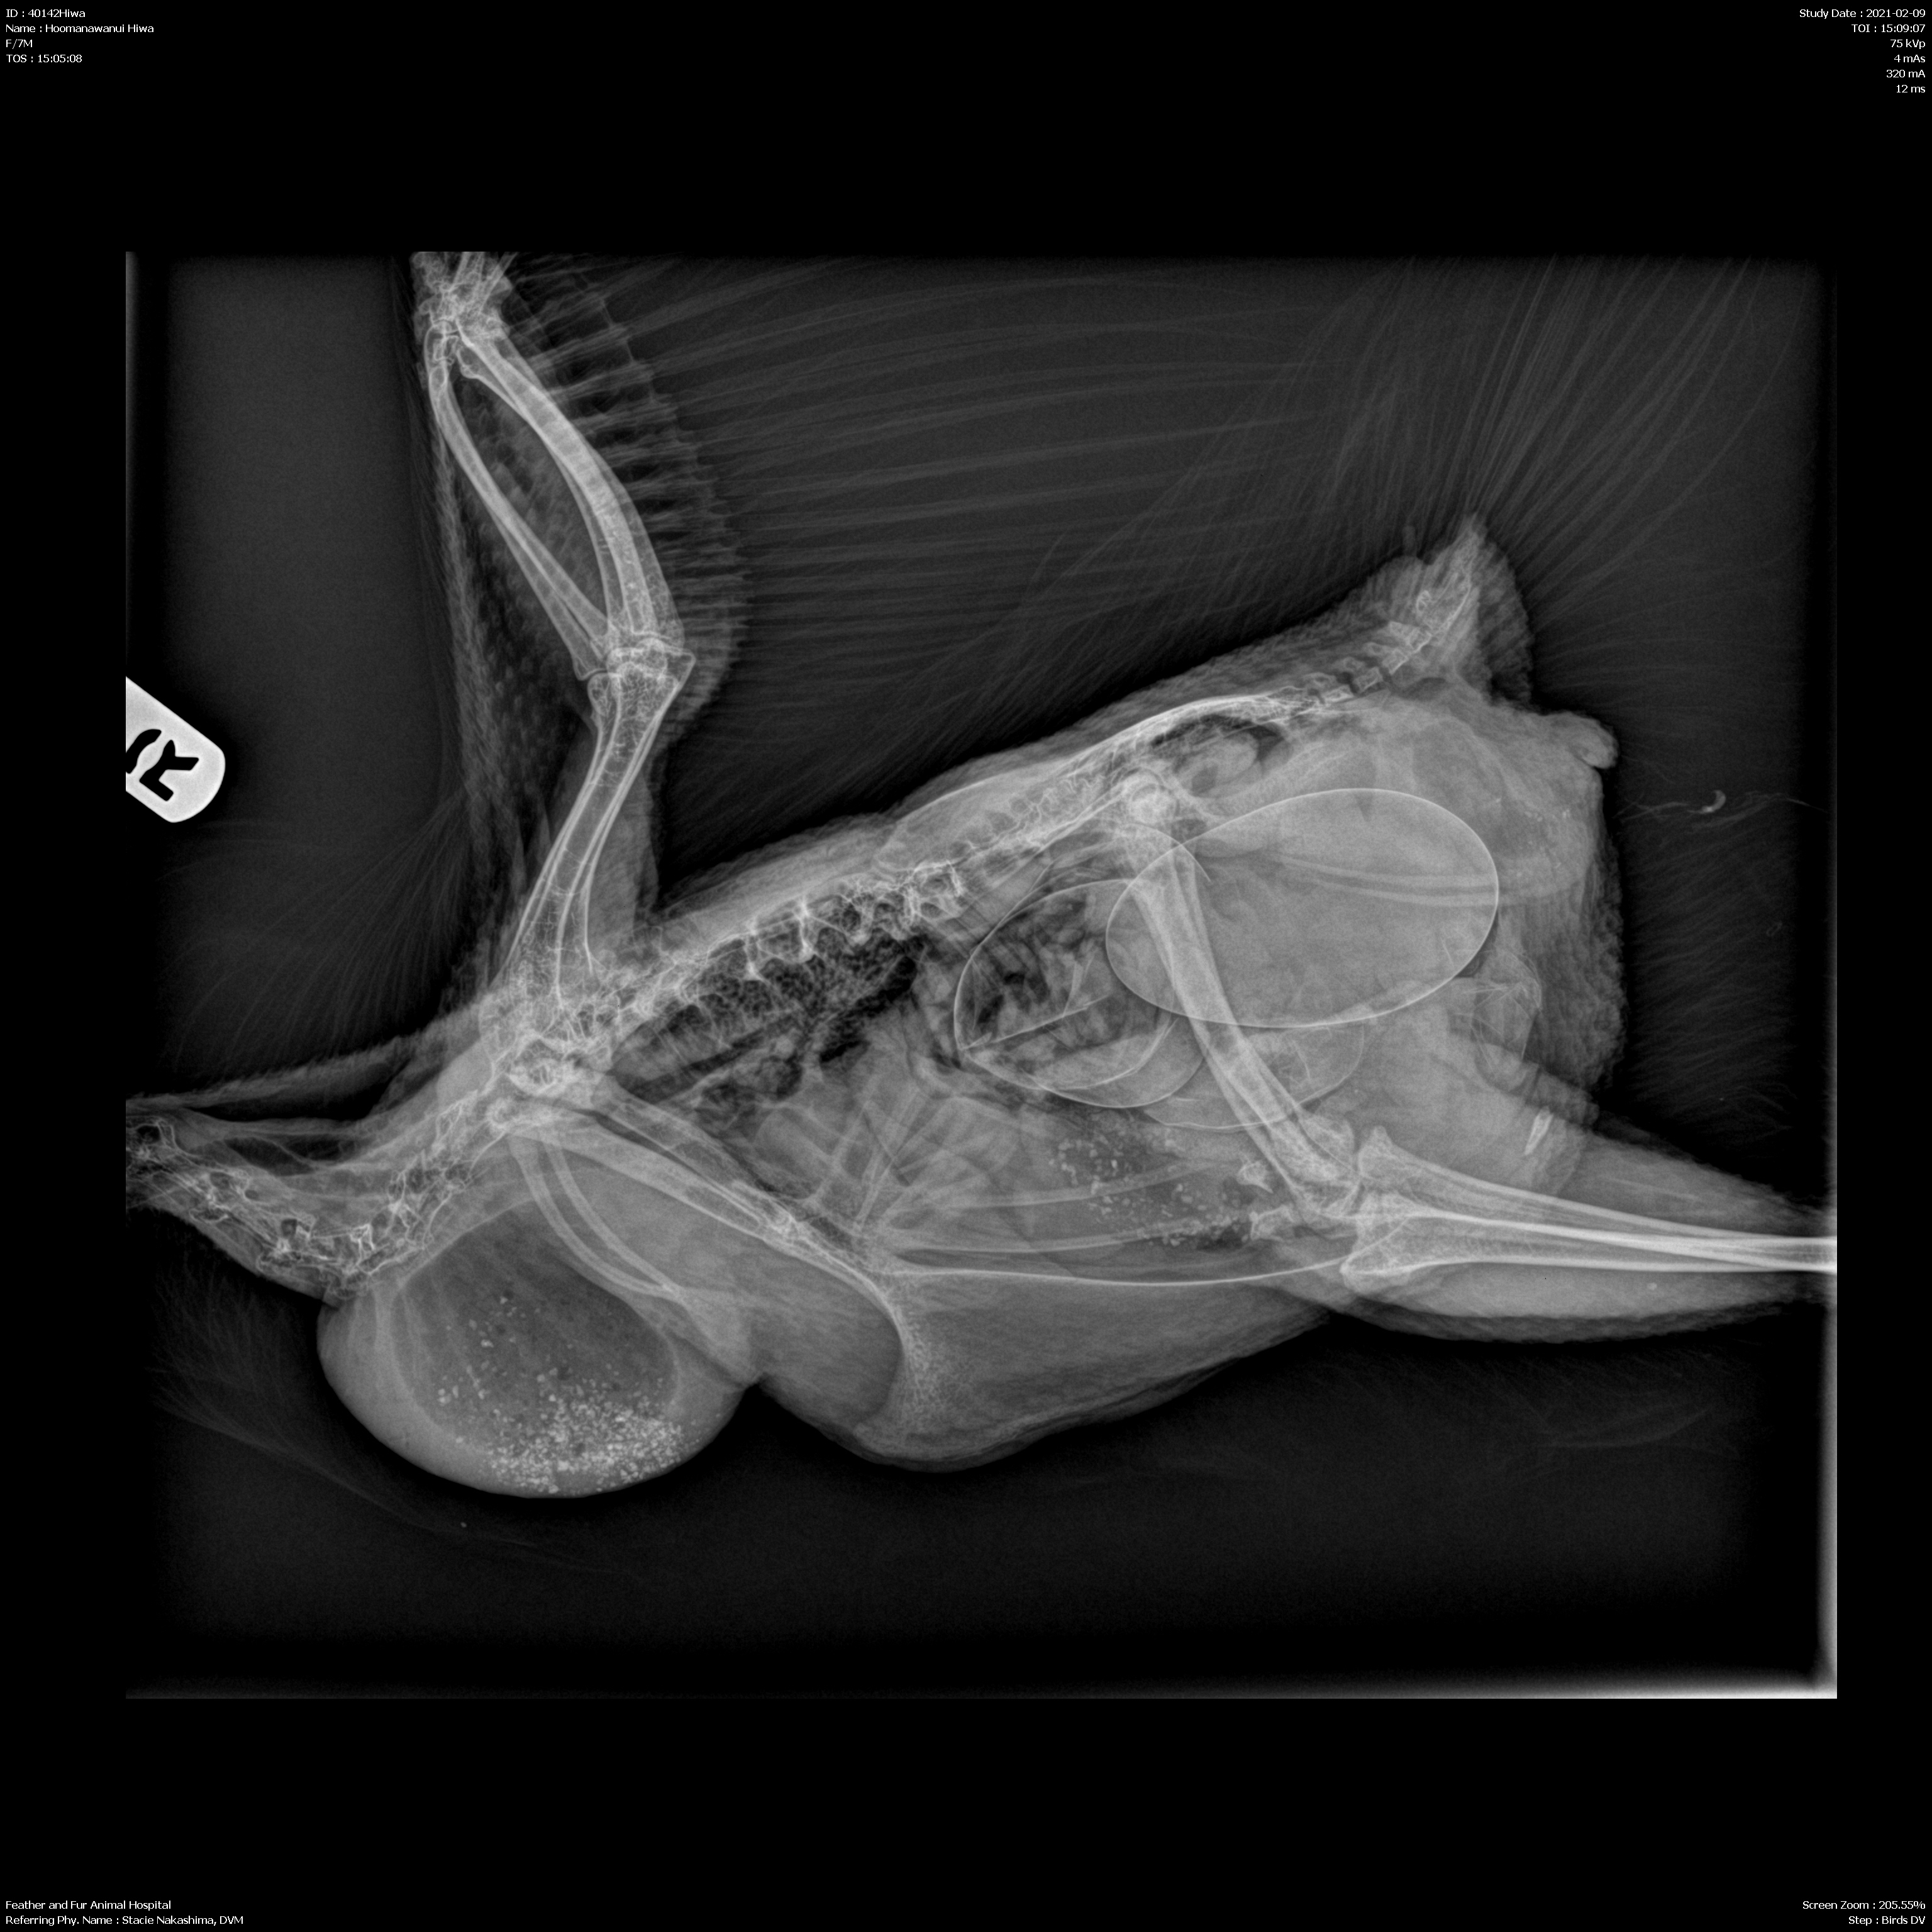

Day 4: After four days of treating her for sour/impacted crop by massaging her crop, Sheri took her to a 24/7 animal hospital with three main Avian Veterinarians. They found that she actually didn’t have sour crop or any kind of gastro-intestinal obstruction. Her x-rays and ultrasound revealed that Hiwa was egg bound and her crop issues were a side effect of the two large, irregular eggs pressing on her digestive tract.

They kept Hiwa overnight and did a digital internal exam and athough they could feel the egg, weren’t sure if it was stuck. The vet also flushed her crop and tube fed her, but could only give her 10cc before she started regurgitating. They recommended she stay several days longer to be tube fed and monitored. She was put on antibiotics (Clavamox) and a pain reliever/anti-inflammatory (Meloxicam). Her normal weight was 3kg; her current weight had dropped to 2.01 kg.